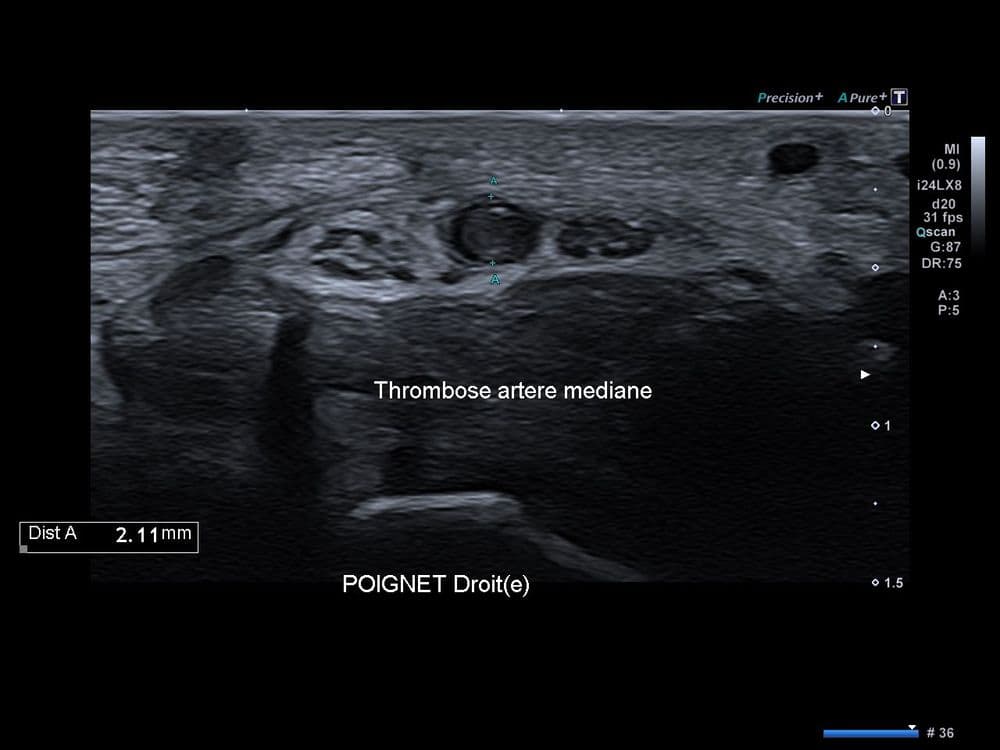

Douleur médiane spontanée du poignet révélant une pathologie vasculaire rare.

US